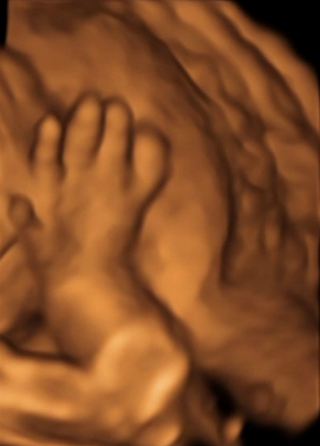

รูปที่ห้า มือและนิ้วมือของน้อง